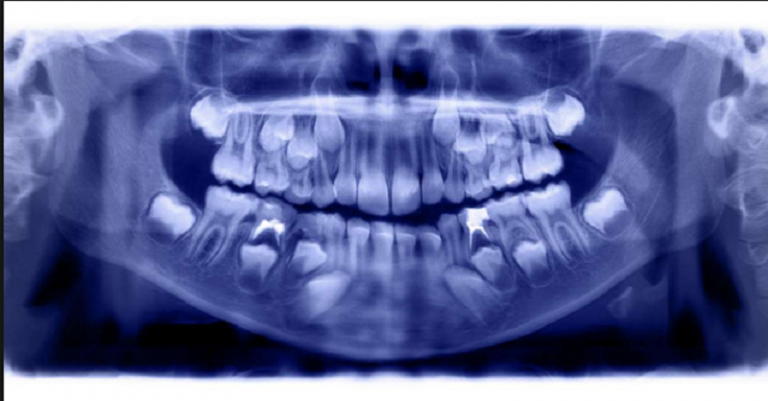

एजेन्सी । भनिन्छ ३२ वटा दाँत भएका मान्छेले बोलेको कुरा पुग्छ । कसै-कसैको २८ वटा पनि हुन्छ । तर भारतमा भने दाँतको विषयमा आनौठो समाचार सार्वजनिक भएको छ ।

तमिलनाडु राज्यको राजधानी चेन्नईमा सात वर्षको केटाको मुखबाट ५२६ दाँत निकालिएको छ । डाक्टरको अनुसार त्यस्तो असामान्य दाँत हुनको कारण मोबाइल टावरबाट उत्पन्न विकिरण पनि हुन सक्छ ।

केहि वर्षदेखि रबिन्द्रनाथको दाहिने गाला सुन्नएिको थियो बुबा एस प्रभुदासले छोराको दाँत बिग्रिएको अनुमान गरेका थिए। तर जब उनले छोरालाई डाक्टरकोमा जाँच गर्न लगे, तब अचम्मको कुरा थाहाभयो ।

रबिन्द्रनाथको मुखमा ५२६ दाँत रहेछ । निजी क्लिनिकमा डाक्टरहरूले रबिन्द्रनाथको शल्यक्रियाका लागि पाँच घण्टा लागेको बताए ।

अब उस्को मुखमा २१ दाँत बाकिँ छ ।